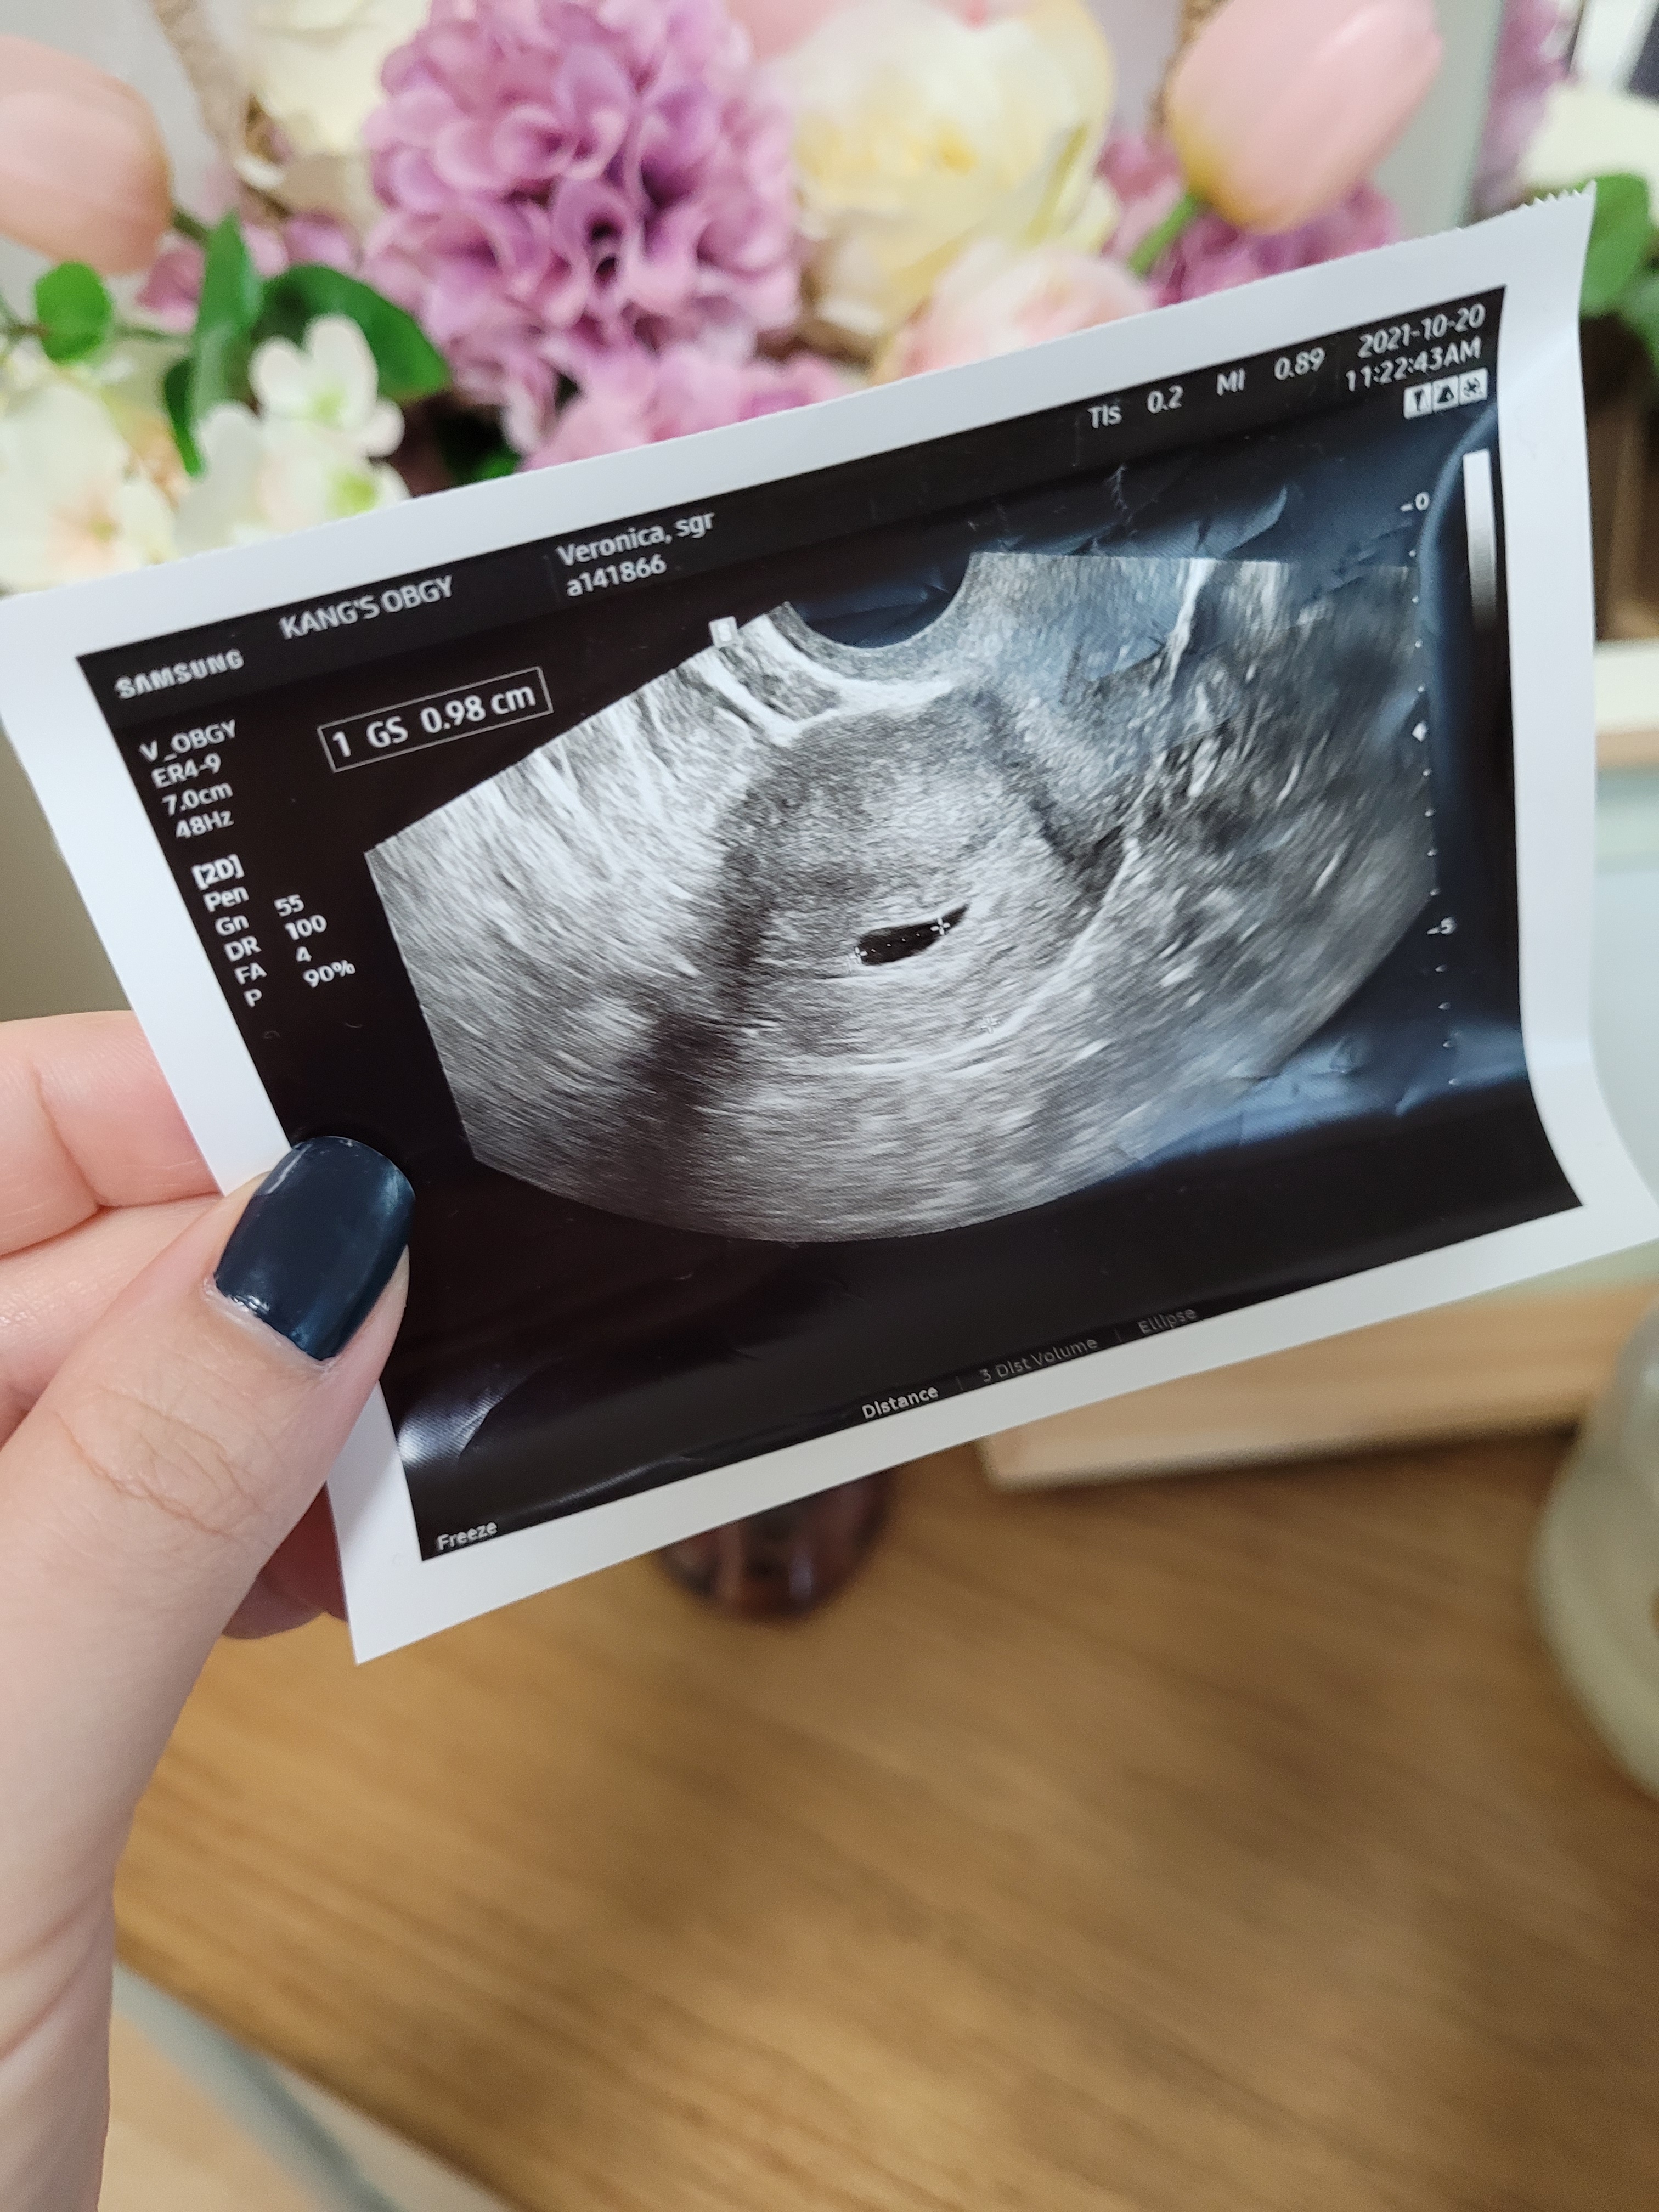

The gestational sac at 5 weeks! This is when we found out for certain that I was pregnant.